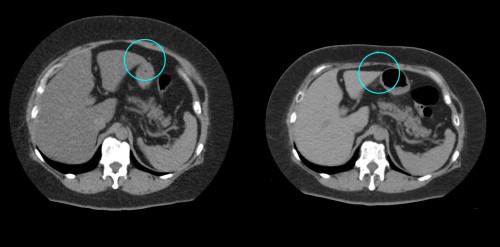

④

50代・男性(ご本人のご厚意で画像提供)

治療内容:チルゼパチド7.5mgの週1回自己注射による脂肪減少と脂肪肝改善

治療期間: 12ヶ月(52週)((用量は2.5mgから開始し最大で15mg。減量効果が得られる必要用量には個人差があります。))

費用:自由診療の場合は9900円(税込)×52(週)=514800円

想定されるリスク・副作用:下記に副作用を記載

※医療広告ガイドラインに準拠して表記

1:脂肪の減少

皮下脂肪の減少(赤色部分)

2:脂肪肝の改善

沈着した脂肪の減少による肝臓の平均CT値の増加(20から50へ)(脾臓の平均CT値は両者とも50)

bluntness of the liver edgeの改善(青色部分)